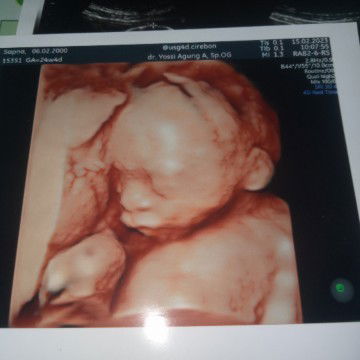

Hallo bunda apa kabarNya? Semoga bunda² disini diberi kesehatan buat bunda & janinNya aamiin🤲🏻 ini hasil usg ku bun kandungan ku saat ini 21 week 6 day

Maasyaallah Tabbarakallah Alhamdulillah🤲🏻 ini adalah hasil usg ku bun, Alhamdulillah sii utun ngga malu² nunjukin mukaNyaa🤗